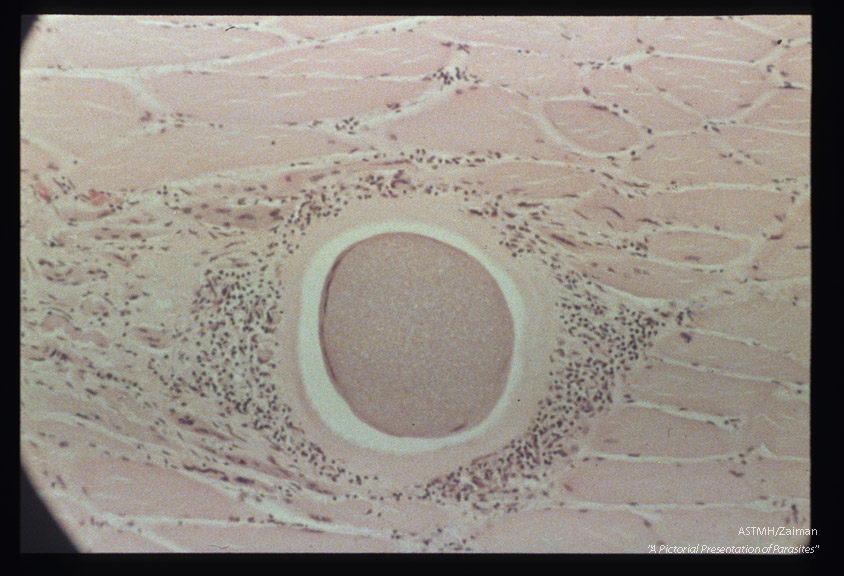

Cysts in striated muscle of reindeer.

Description: Cysts in striated muscle of reindeer.